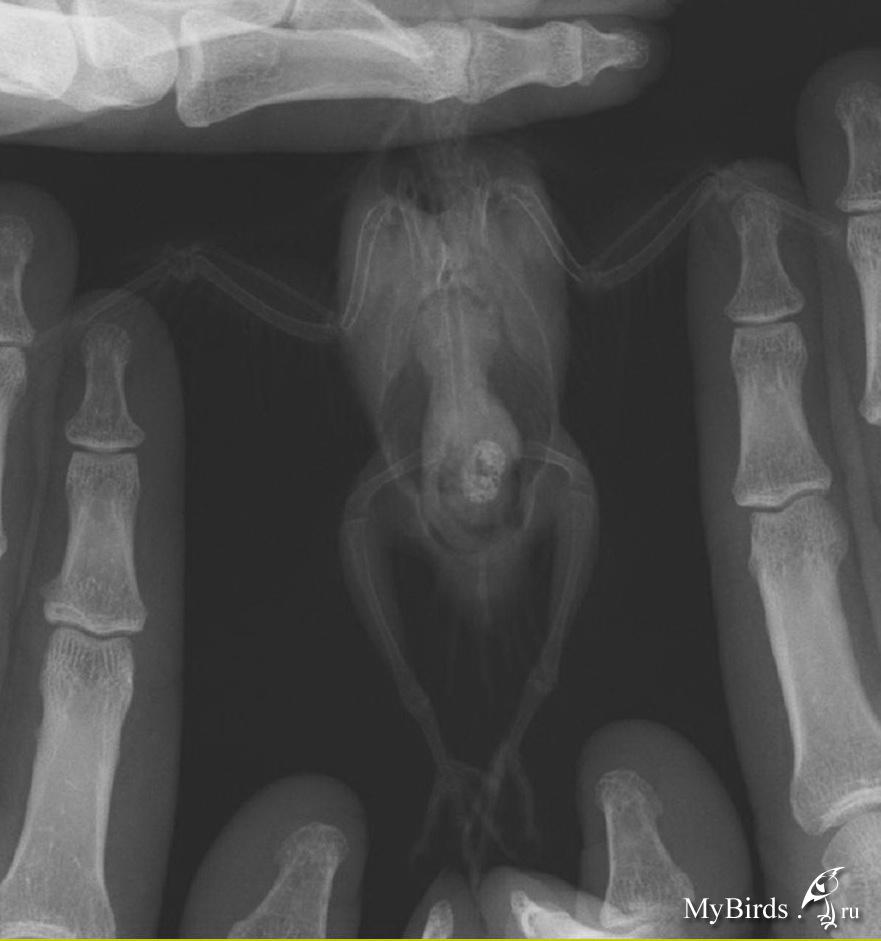

Сегодня, сдала анализ на бактериальный посев волнистику и розелле. Через неделю будут готовы результаты. И сделала рентген волнистику, выкладываю снимки

post-21892-1290988329_thumb.jpg post-21892-1290988344_thumb.jpg

Я делала рентген в Шанс Био на Цветном бульваре. Записали диск с программой, как и ранее. Если плохо видно, то я могу выслать на почту программу со снимками.

Lyalka, на рентгене все еще видно затемнение на суставе, хоть оно и стало заметно меньше. Или, возможно, воспаление практиески прошло, а теперь заново начинается.

Стоит повторить компрессы, предложенные Тимериным.

Крупно:

___1.JPG ___2.JPG